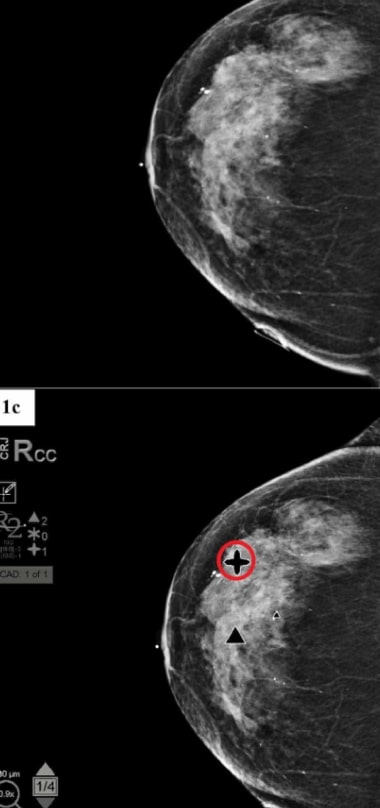

Hologic CAD (Computer Aided Detection)

The Hologic CAD system enhances diagnostic accuracy by reducing observational oversights. It also provides advanced software analysis that identifies potential abnormalities with precision.